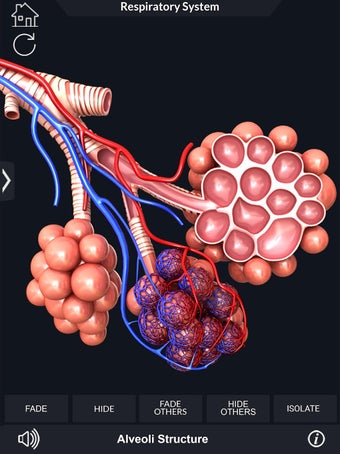

呼吸器系の解剖学は、肺、気管、およびすべての気道を含む呼吸器系の解剖学の研究です。最も一般的なアプローチは、系を上部と下部に分割することです。上部には気管、主気管支、および終末および前頸気道が含まれます。下部には肺と最小の大きさの末梢気道が含まれます。これらの部分それぞれには特徴的な外観と機能があります。

このアプリケーションは、高度にリアルな呼吸器系のモデルです。ユーザーは任意の角度および任意の平面から呼吸器系の解剖学を表示できます。ユーザーは360°回転し、ズームインおよびズームアウトして解剖学をよりよく研究することができます。ユーザーはまた、画面に描画するためのさまざまなツールを使用して写真を撮ることもできます。